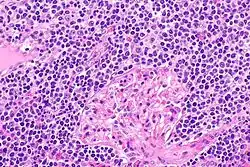

| EMZL infiltrating kidney tissue. | |